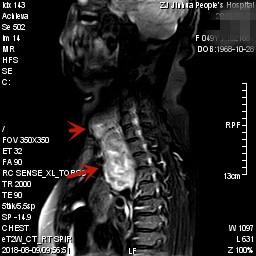

上图均示MRI下的肿瘤情况,红色箭头示肿块

上图示颈部与胸内的病灶关系密切,但绿色箭头处似有分界,仅少许相连